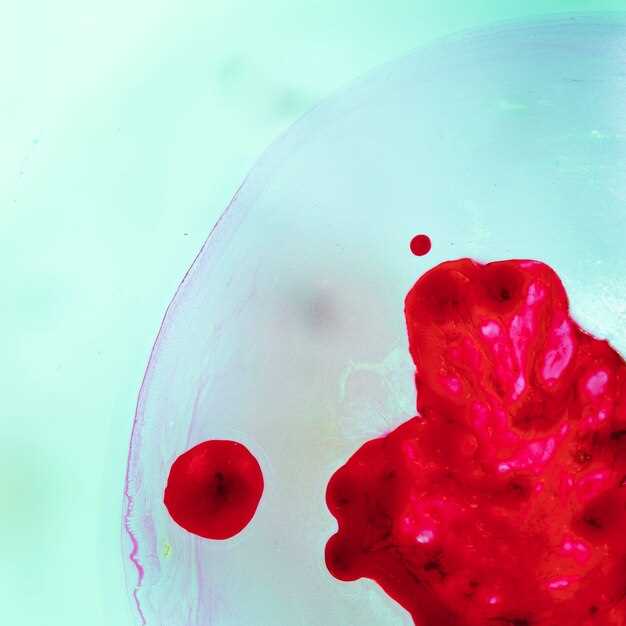

Высокий уровень гемоглобина в крови нередко становится предметом беспокойства как для пациентов, так и для врачей. Гемоглобин – это белок, содержащийся в эритроцитах, который отвечает за транспортировку кислорода от легких к тканям. При этом, повышенный уровень гемоглобина может сигнализировать о разнообразных заболеваниях или состояниях организма, требующих внимания. Понимание причин этого явления и его последствий является ключевым для эффективного лечения и профилактики.

Высокий уровень гемоглобина, часто называемый полицитемией, может иметь серьезные последствия для здоровья человека. Увеличение концентрации гемоглобина в крови приводит к повышению вязкости крови, что затрудняет ее передвижение по сосудам. Это состояние может привести к образованию тромбов, что значительно увеличивает риск инсульта и инфаркта миокарда.